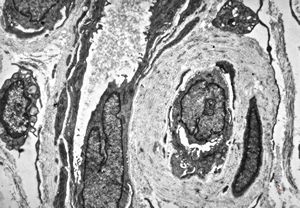

F, 48y. | lupus erythematodes … multiplicated vascular basement membrane